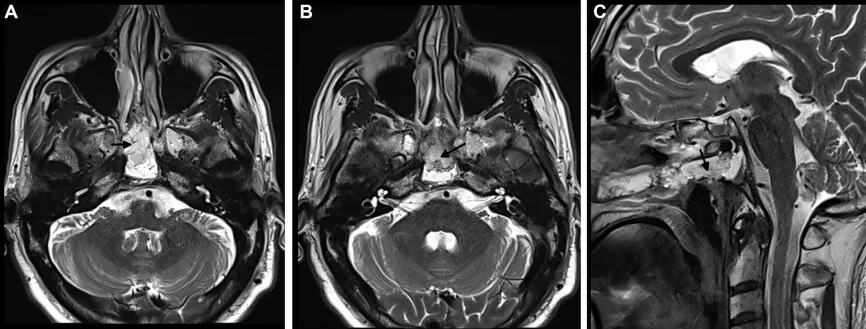

该患者的磁共振成像(MRI)结果显示,他的病变位于斜坡的上部和中部,同时存在一个较大的鼻中隔穿孔,提示在之前的内镜活检过程可能已经损伤了鼻中隔动脉,从而导致他持续地鼻出血,极大地影响了日常生活质量。经过对患者的全面检查和评估,福教授认为应当进行肿瘤切除以及血管修复手术。

术后MRI显示肿瘤被完全切除,手术顺利。患者术后恢复顺利,期间没有鼻部不适。在2个月随访时,内镜检查显示鼻窦上方由术前的白色粘膜转变成健康的粉红色黏膜,恢复正常。

术后MRI影像明确肿瘤全切情况,以及用于重建的自体脂肪